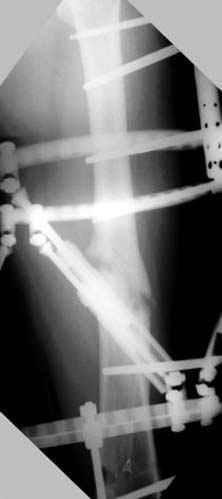

Несколько снимков из моей коллекции, чтобы разьяснить, почему мы до сих пор делаем различные варианты остеотомии.

На рисунке N1 предоперационный план лечения ложного сустава шейки бедра- линия ложного сустава, угол и направление введения импланта, клиновидная остеотомия в градусах и миллиметрах, второй снимок после коррекции, расчет, на сколько удлиняется конечность и размеры импланта;

N3 рисунок окончательный снимок, после операции моя рентгенограмма должен выглядеть примерно как эта картина. На N4 снимке клин перед удалением; N5 послеоперации 3 нед.; N6 окончательная рентгенограмма.